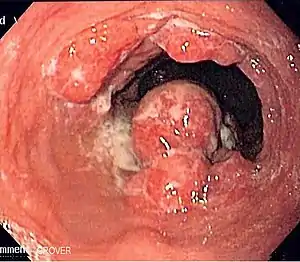

Endoscopic image of an esophageal adenocarcinoma

Esophageal cancer is cancer arising from the esophagus—the food pipe that runs between the throat and the stomach.[2] Symptoms often include difficulty in swallowing and weight loss.[1] Other symptoms may include pain when swallowing, a hoarse voice, enlarged lymph nodes ("glands") around the collarbone, a dry cough, and possibly coughing up or vomiting blood.[1]

The two main sub-types of the disease are esophageal squamous-cell carcinoma (often abbreviated to ESCC),[9] which is more common in the developing world, and esophageal adenocarcinoma (EAC), which is more common in the developed world.[2] A number of less common types also occur.[2] Squamous-cell carcinoma arises from the epithelial cells that line the esophagus.[10] Adenocarcinoma arises from glandular cells present in the lower third of the esophagus, often where they have already transformed to intestinal cell type (a condition known as Barrett's esophagus).[2][11] Causes of the squamous-cell type include tobacco, alcohol, very hot drinks, poor diet, and chewing betel nut.[3][4] The most common causes of the adenocarcinoma type are smoking tobacco, obesity, and acid reflux.[3]